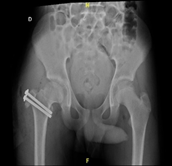

A 12-year-old male patient, who began medical controls in our service in 2018, diagnosed with Legg-Calvé-Perthes disease of the right hip (Figure 1), presenting pain when standing, agitated gait, and claudication. In 2022 in tomographic control (Figure 2) and CT with 3D reconstruction (Figure 3) that evidence right coxa magna and alteration of the femoral sphericity with CAM type morphology, associated with pain and limitation of range of motion, was the reason for which it was decided to perform surgical intervention. Physical exam: Pain and limitation of range of motion (right/left flexion 100°/100°, right/left internal rotation 28°/45°, right/left external rotation 12°/20°, limited abduction due to pain in the right lower extremity).

Figure 1 AP and Lowestein Pelvis X-ray from 2018, showing Legg-Calvé-Perthes disease of the right hip.

1. AP and Lowestein Pelvis X-ray from 2018, showing Legg-Calvé-Perthes disease of the right hip.